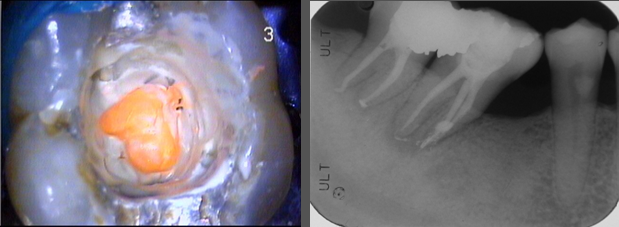

修形後,以垂直熱充填封填根管

研究報告東方人的下顎第二大臼齒的C形根管大約有3成,這位患者有二次蛀牙,因此進行根管治療,使用顯微將根管徹底清潔並封填之,術後情況良好